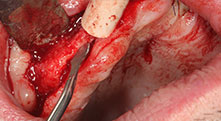

Würden Sie uns kurz beschreiben, wie Sie zum Beispiel beim Mobilisieren von Knochenblöcken für Transplantationen vorgehen?

Bratu: Wir bevorzugen Knochenentnahmen von der Linea obliqua externa des posterioren Unterkiefers, nicht aus der interforaminalen Region. Nach der Weichgewebsinzision verwenden wir die neuen Sägen, um den Umfang der Knochenentnahme zu definieren. Wir erledigen damit in fast 80 Prozent der Fälle auch die gesamte Präparation. Zusätzlich verwenden wir eventuell andere Piezo-Instrumente und zuletzt einen Meißel, um den Block zu mobilisieren. Das ist für uns eine sehr effektive Operationstechnik.

Verraten Sie uns noch ein paar chirurgische Tipps und Tricks aus Ihrer Klinik?

Bratu: Wir augmentieren im seitlichen Unterkiefer gern mit der Sandwich-Technik. Dabei wird ein Knochendeckel mit der Piezosäge präpariert und das krestale Fragment mit Mikroschrauben fixiert. Dazwischen platzieren wir eine Mischung aus autologem Knochen und xenogenem Knochenersatzmaterial. Das funktioniert sehr zuverlässig. Bei Kieferkammspaltungen im Unterkiefer sollten Sie nie auf ausreichend dimensionierte vertikale Schnitte verzichten. Sonst kann der Knochen leicht frakturieren.